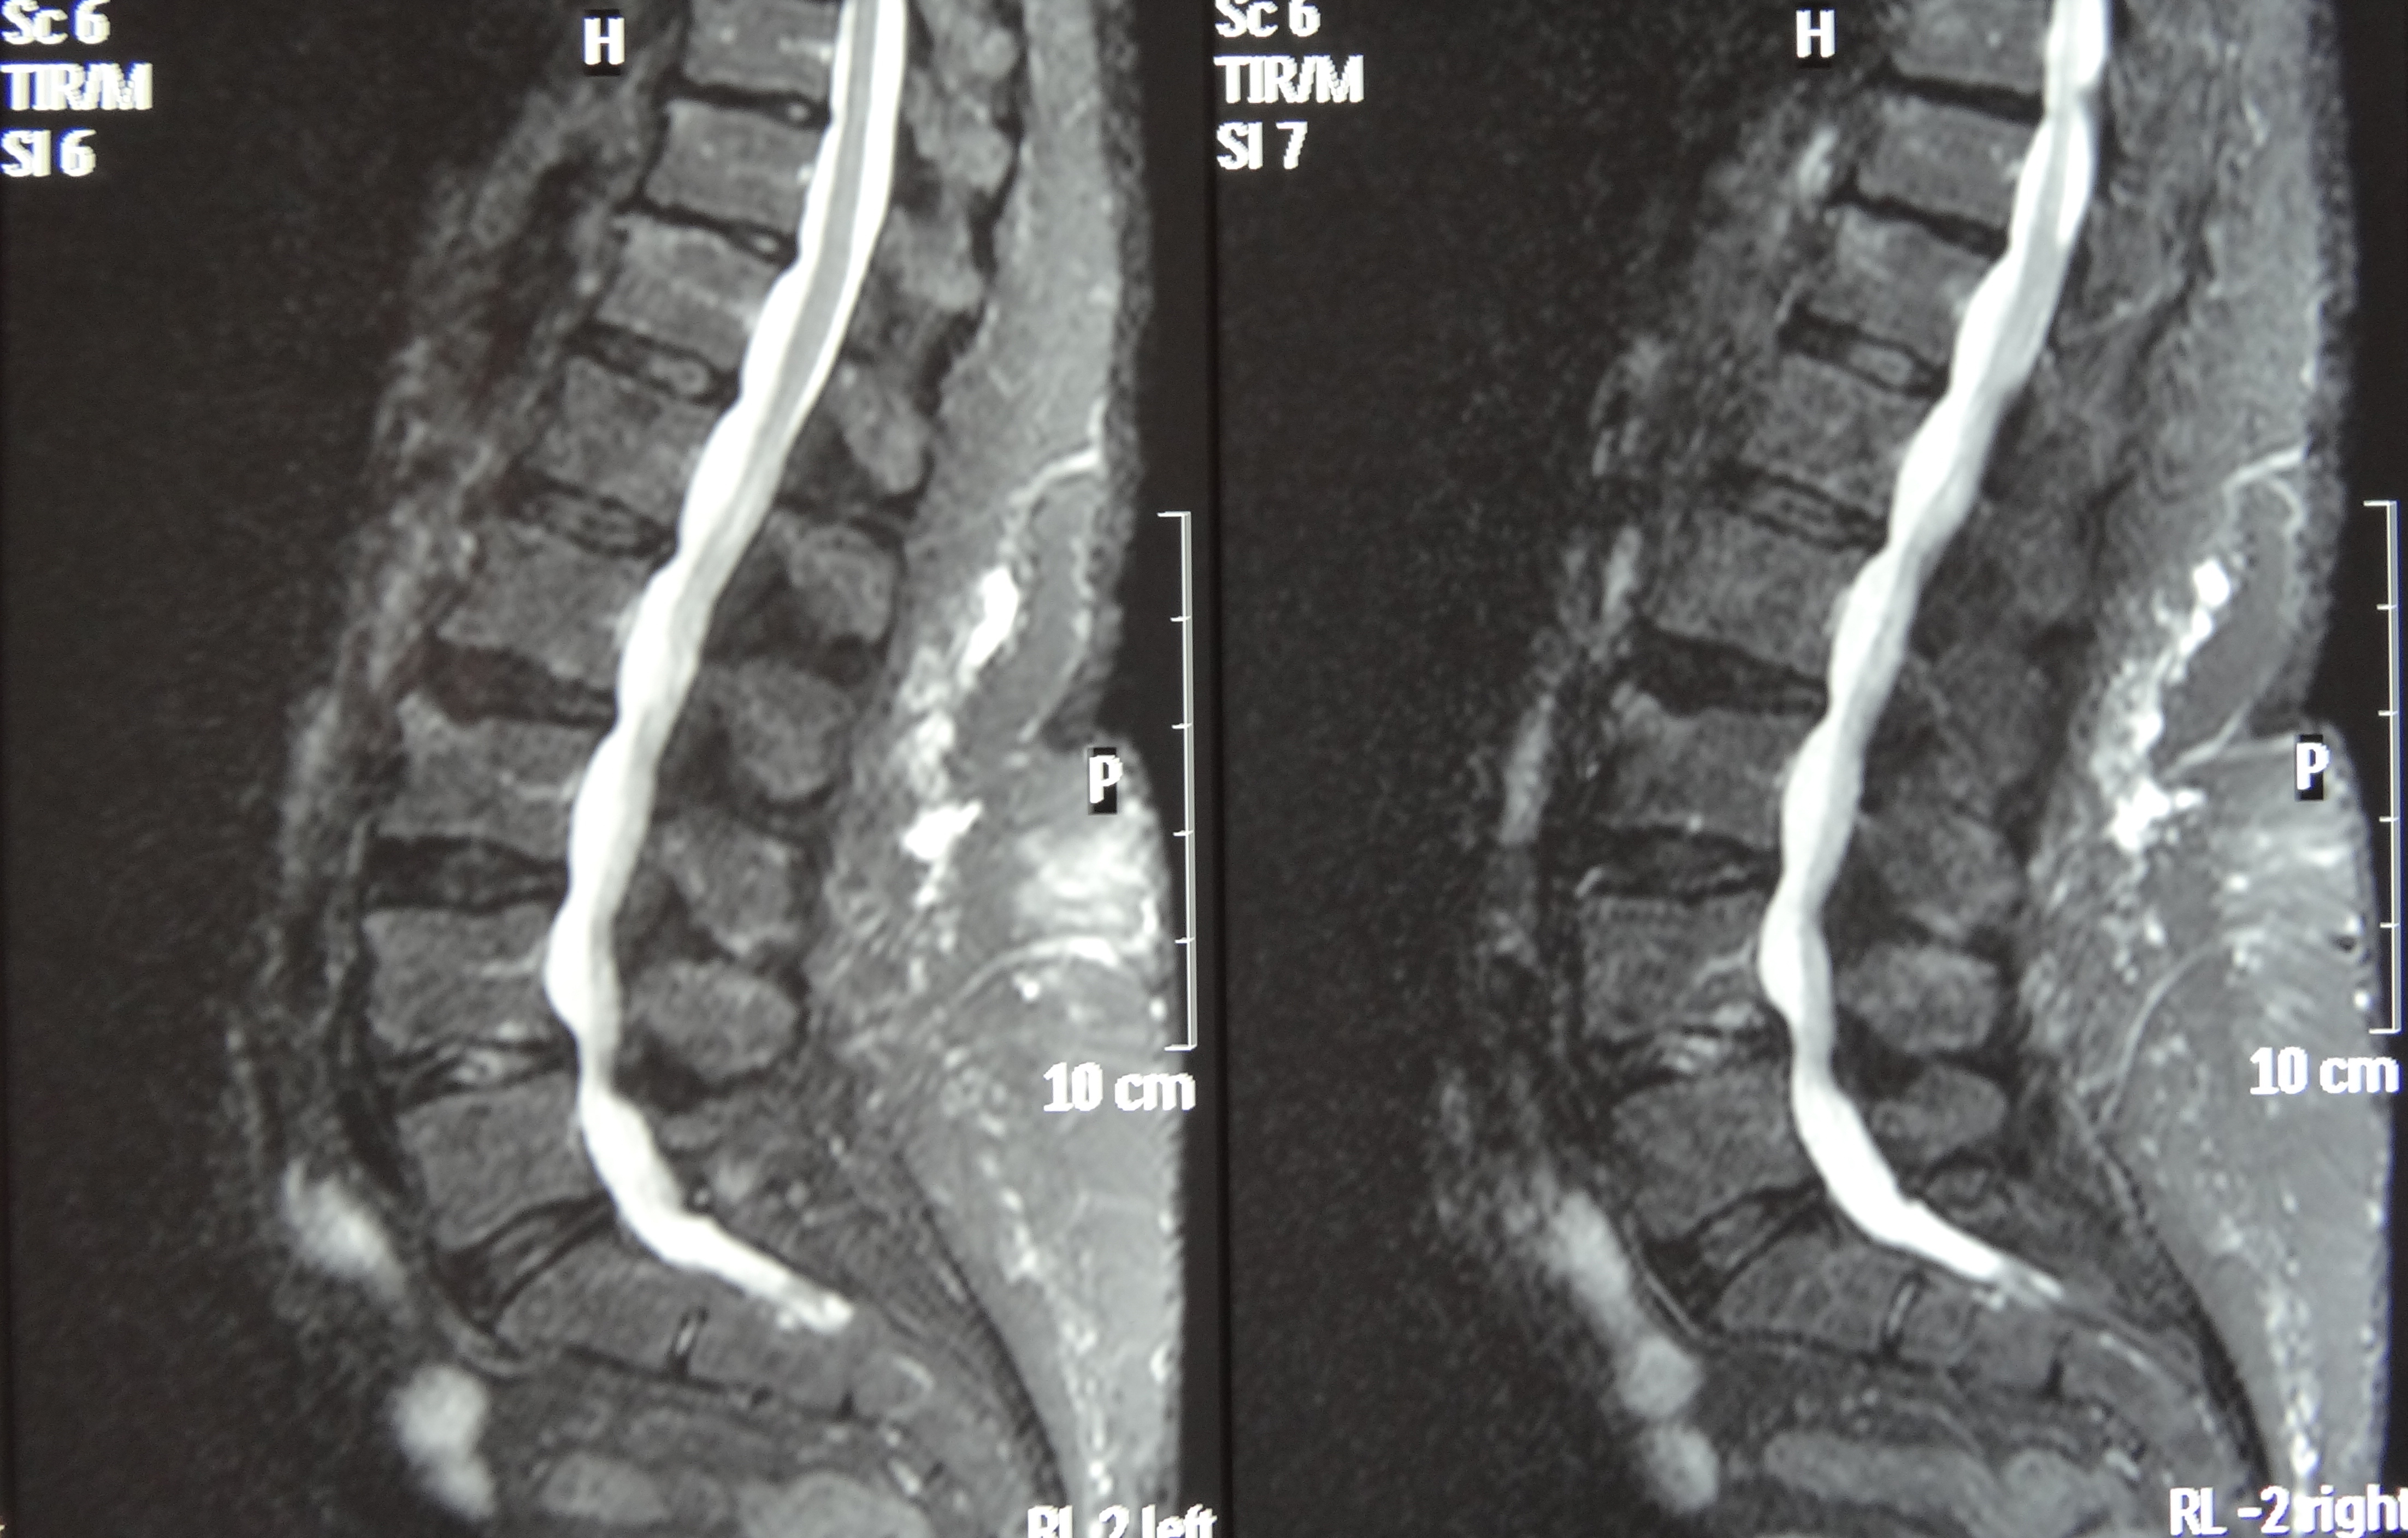

This patient presented with an ultrasound demonstrating a baseball-sized Baker's cyst behind the knee. The "after" film was taken 4 months after the 8th treatment of prolotherapy. He is now enjoying being pain and Baker’s cyst free. At three year follow-up, the cyst had not returned.[/toggle_content]

This patient presented with shoulder pain that interfered with work and exercise. The visible fluid-filled cysts on the “Before" MRIs are from chronically injured rotator cuff tendon roots.

The patient underwent treatments of a highly specialized fine-needling technique pioneered by Dr. Tallman.The follow-up MRI was done 2 months after his 6th treatment. He was released with a pain-free, full range of motion with unrestricted activities.